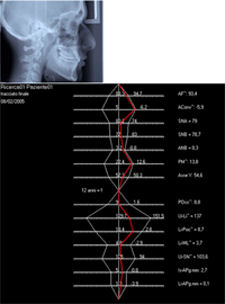

Se evaluó al paciente luego de tres años de haber culminado el tratamiento funcional y se evidenció el crecimiento mandibular complementario, con un SNB de 78 grados y un ANB de 1 grado, (Fig. 7: a-b). La posición de los incisivos superiores e inferiores con respecto a las bases óseas, se mantuvo estable en el tiempo y su patrón de crecimiento rotacional continuó con su tendencia braquifacial. (Fig. 4, a-b)

Fig 7 (a-b): Análisis cefalométrico final (según Illinois)

Se evaluó la distancia entre los puntos óseos Condileo-Pogonio (Co-Pg) al inicio de la terapia funcional, la cual tuvo un valor de 110 mm para pasar a 122 mm al finalizar el tratamiento. También se evaluó la distancia entre el punto Articular y Pogonio (Ar-Pg), la cual pasó de 103 mm al inicio del tratamiento a 115 mm al final del mismo. Como se evidencia, el maxilar inferior además de asumir una posición adelantada, incrementó su crecimiento en forma considerable, mejorando la relación basal con el resto de las estructuras óseas.